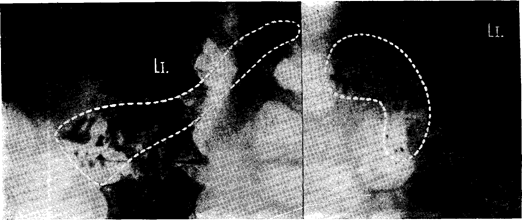

Рис. 12" Кальцификация поджелудочной железы, свидетельствующая о хроническом пан­креатите, в проекции: а) передне-задней, б) боковой. (Случайная находка у 60-летнего муж­чины, не предъявлявшего жалоб со стороны пищеварения.)

РЕНТГЕНОЛОГИЧЕСКОЕ ИССЛЕДОВАНИЕ а) Наиболее несложным и имеющим наибольшее значение является обнаружение кальцификаций на нативном снимке живота (рис. 123). Они бывают рассеяны в виде разнообразных агломератов по ходу поджелудочной железы и состоят из углекислого фосфорнокислого кальция. Они являются достоверным признаком перенесенного некроза. Иногда они определяются уже после первого приступа пакреатита, частота их возрастает по мере длительности заболевания и предполагают, что они встречаются даже у 50% всех больных панкреатитом. В связи с тем, что хронический панкреатит во многих случаях трудно распознать, рентгенологическое выявление кальцификаций часто является первым пока­зателем этого диагноза.

Кисты и кистоиды поджелудочной железы в зависимости от локализации вдавливаются в контуры малой или большой кривизны желудка (рис. 124а, б) или также как опухоли головки поджелудочной железы раздвигают дуоденальное окно (рис. 124в, 125). Увеличение тела поджелудочной железы проявляется расширением ретрогастрального пространства (рис. 1276).

Рис. 124. Деформация желудка псевдокистой поджелудочной железы: а) псевдокиста в хвосте сдавливает большую кривизну, б) псовдокиста в толе поджелудочной железы раздвигает апгулярную область. прямого прокалывания расширенного протока. Она ценна для доказательства проходимости панкреатических протоков, воспаления и опухолей поджелудоч­ной железы, но она небезопасна, так как может вызвать острый некроз.